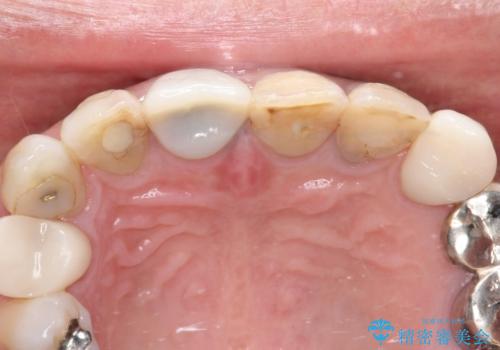

- 前歯の変色を主訴に来院されました。

歯茎のラインも整っていなかったため、手術を行いきれいな被せ物をいれることができました。